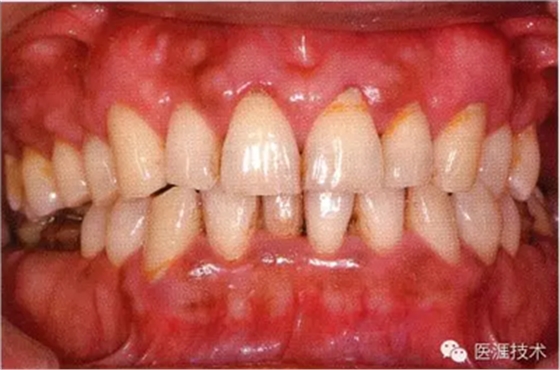

44歲牙周炎女性的臨床照片

44歲患有糖尿病病史(未治愈)。菌斑控制不良。通過牙周探診,全頜有4~8mm的牙周袋,在X光片中可以看到上頜前牙處中度牙槽骨吸收,磨牙處重度牙槽骨吸收。二次齲齒和根面齲齒也有發(fā)生??梢钥吹礁∧[性腫脹,收到刺激后會出血。